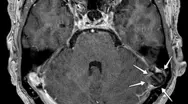

Det lille brok ind i AG kaldes samlet set BHAG, hvilket står for Brain Herniations into Arachnoid Granulations (se billedet). Brokket kan være af forskellig størrelse, men omkring 10 mm er almindeligt. Det kræver således tynde snit og høj opløsning for at kunne se dem. De moderne skannere er netop karakteriseret ved at skanne med tyndere snit og højere opløsning, så man må forvente at se flere af dem fremadrettet.

De sjældne forandringer kan ses ved en MR-scanning. Emnet er endnu ikke beskrevet i dansk litteratur, og der er ikke megen viden om det. Forandringen er sagt i enkelthed den, at en del af hjernen har dannet et “brok” ind i en normal struktur tilhørende hjernens hinder, de såkaldte arachnoide granuleringer (AG), som blandt andet ligger inkorporeret i de store venestrukturer (sinus), der leder blodet fra hjernen. AG er normalt af betydning for at lede hjernevæsken bort fra rummet omkring hjerne og rygmarv og er dermed med til at bortskaffe affaldsstoffer med mere via blodbanen.